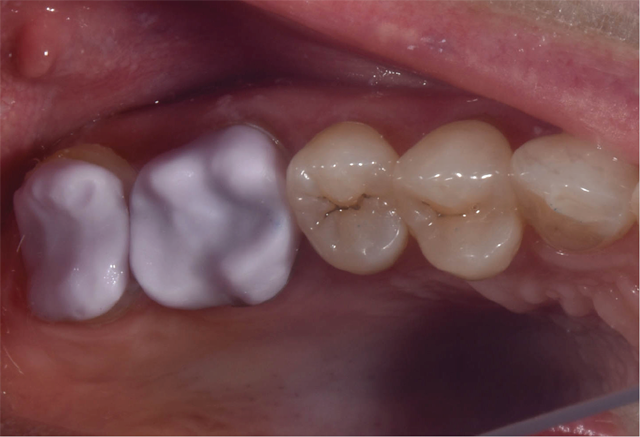

A 50-year-old female with no significant medical history presents for same-day, all-ceramic, full coverage onlay restorations on tooth No. 14 and No. 15. Existing restorations include No. 14OL and No. 15DO defective composites with open margins and recurrent caries (Fig. 1). The patient reports infrequent cold sensitivity localized to No. 14 and No. 15.

Fig. 1 Fig. 2